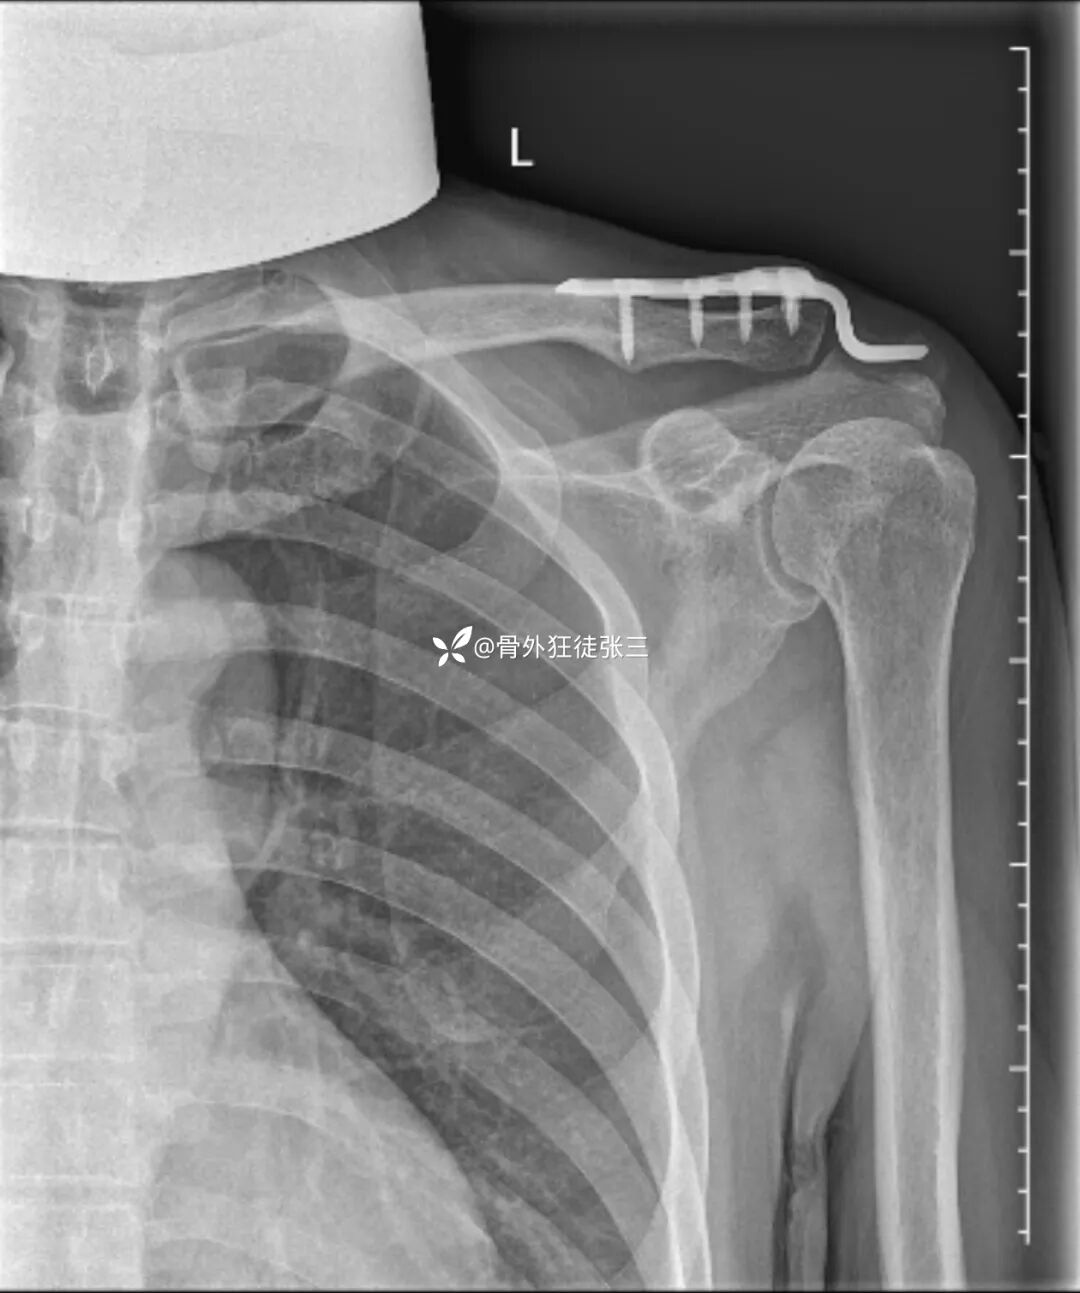

病例三:

取出后,查体肩锁关节稳定

复查关节间隙正常

术中麻醉下顺便给患者肩关节做一个手法松解

术后第2天,今天,查房患者诉

“肩膀(关节)前所未有的轻松”